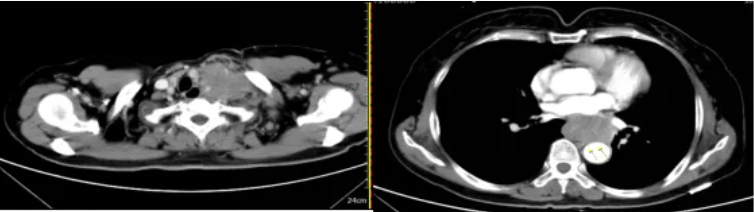

颈部、胸部增强(2019-11)CT示:

食管中下段不规则软组织肿块,考虑食管癌,伴纵隔内、左侧锁骨上、下窝及左侧腋窝、左侧颈根部及胸廓入口处多发肿大淋巴结,考虑转移瘤并侵犯食管上段。

图3 颈部、胸部增强CT(2019年11月)